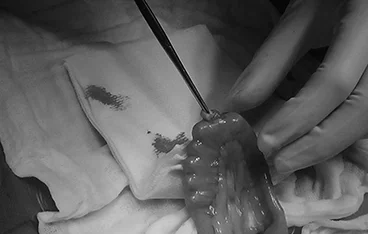

담낭절제술 + 담관 Flushing

• 담낭절제술